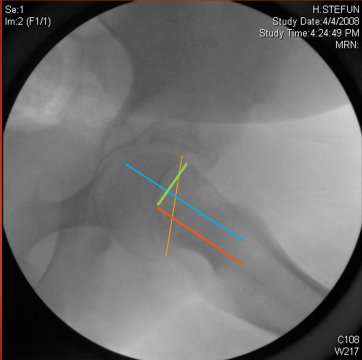

Slipped capital femoral epiphysis

SCFE — slip deformity analysis.